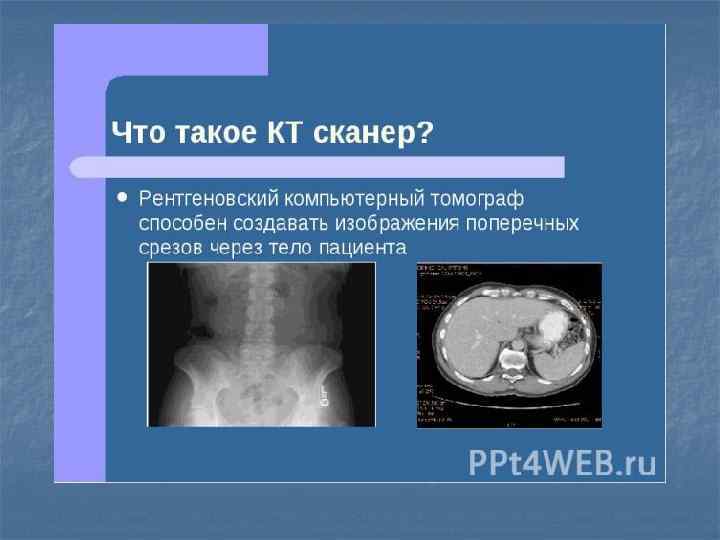

Показания n n n n n Обзор органов брюшной и грудной полости (наличие воздуха, жидкости, метастазов, инородный предметов) Травма костных структур Воспалительный процесс(пазухи черепа, остеомиелит) Дегенеративные изменения позвоночника и суставов Рентген-анатомия органов брюшной полости(желудок, кишечник) Опухоли ЖКТ, легких, реже головного мозга, костей Исследование функций почек и ЖКТ(рентгенография) Аномалии развития органов грудной и брюшной полости (мегоколон, долихосигма, болезнь Гиршпрунга, подковообразная почка, «бычье сердце» и т. п. ) Скрининг заболеваний легких(флюорография)

Показания n n Опухоли и метастазы Кисты, абсцессы и паразитарные кисты Сочетанная травма Воспалительные процессы(пневмония, селликозы, гепатиты, артрозы)